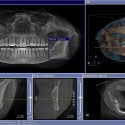

Dental Imaging – X-ray technology allows dentists to diagnose and treat dental problems not yet visible to the naked eye, including early tooth decay, gum disease, abscesses and abnormal growth. It is almost impossible to imagine the practice of dentistry without x-ray pictures (radiographs).This diagnostic tool has prevented untold suffering and saved countless teeth.

Dental X-Ray & Imaging Centre is among the leading Digital Dental Imaging Service Providers in Nairobi, Kenya. This digital x-ray technology uses a small electronic sensor placed in the mouth to capture an image, which can be called up instantly on a computer screen.

• Offers better & more reliable imaging results/picture. Digital x-rays enable our experienced provider to instantly detect abnormalities in teeth, gums, enamel as well as tumorous masses, cavities & hidden dental structures

• Gray-scale resolution of 256 colors compared to 16 to 25 shades on conventional film, allowing for a more detailed, accurate analysis

• Images can be enlarged, adjusted, and saved for future reference

Digital Imaging is the ability of the operator to post-process the image. Post-processing an image allows the operator to manipulate the pixel shades to correct image density and contrast. Images can be stored in a computer and can be viewable on the same computer screen or be printed on paper or film. The images can be viewed in more than one room and can be used in conjunction with pictures obtained with an optical camera to enhance your understanding of treatment.